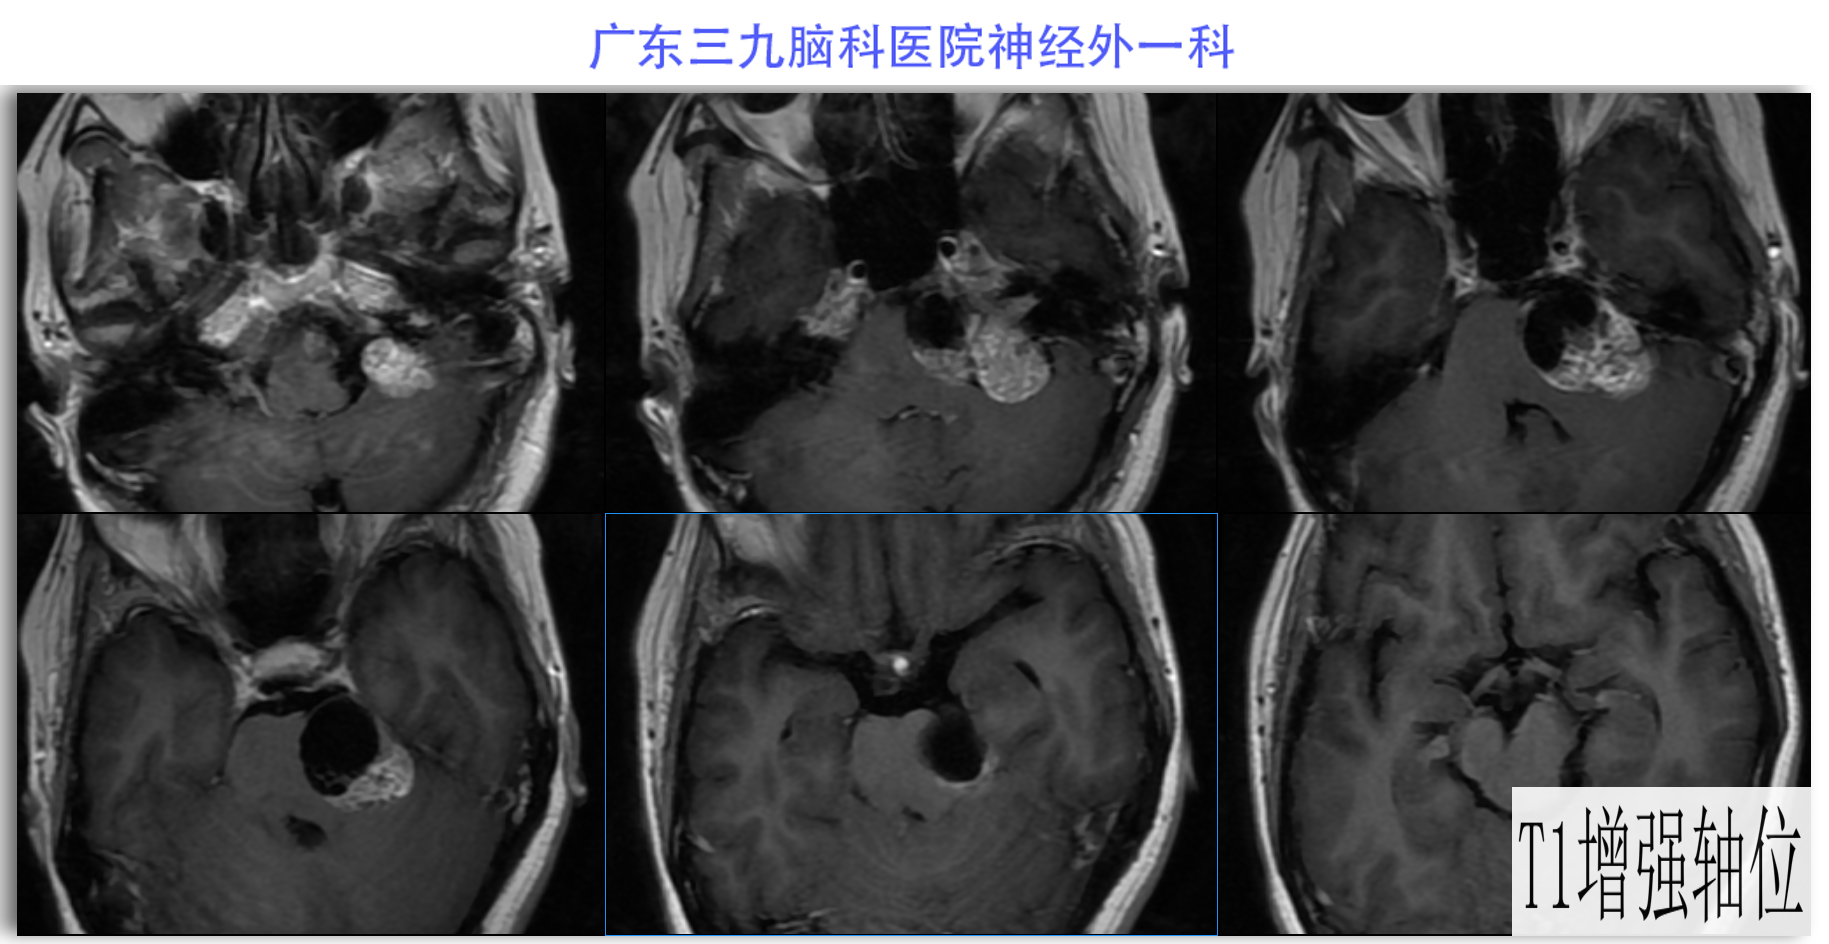

陈某某,女,41岁,因“左侧面部麻木3月余,吞咽困难半月余”于2024-02-17入院。患者3个月前出现左侧面部麻木,偶尔伴有头晕和左侧流泪,但没有听力下降或耳鸣。同时,患者也出现肢体乏力和行走不稳,但未接受任何治疗。半个月前,患者发现吞咽硬质食物稍有困难,同时左侧面部麻木加重。因此,前往当地医院就诊,并进行头颅MR检查,结果显示左侧CPA区存在占位性病变。为了进一步治疗,患者转诊至我院就医。术前检查显示:左侧角膜反射减弱,左侧鼻唇沟略微变浅,伸舌稍微右偏,咽反射迟钝。门诊诊断为“左侧巨大听神经瘤”,收治至我科进行住院治疗。手术过程顺利,术后患者恢复良好,面部轻度瘫痪与术前相同。术后病理检查结果确认为听神经瘤。